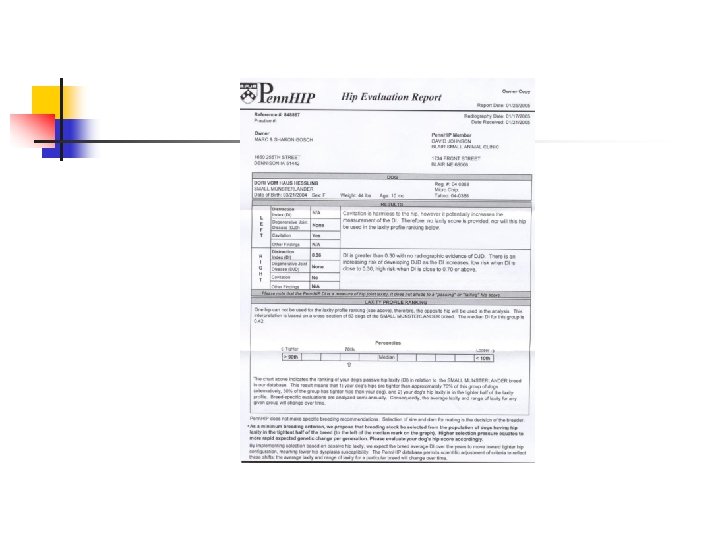

Distracted or Penn. HIP method n n Refers to a specific diagnostic technique of hip laxity information. More reliable indication of hip laxity than extended view. Stress radiographic procedure with 3 views (compression, standard extended, and distraction view). To perform this method, veterinarian or technician must be certified.